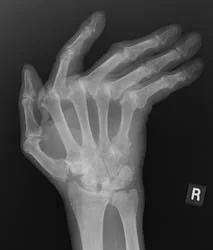

Rheumatic diseases range from very common problems such as osteoarthritis, gout and tendon disorders, to more complex autoimmune conditions such as rheumatoid arthritis, lupus and vasculitis, where the immune system becomes overactive and targets the body’s own tissues. Early, accurate diagnosis and tailored treatment are key to controlling inflammation, preventing joint and organ damage, and maintaining long-term health.

• Rheumatoid Arthritis